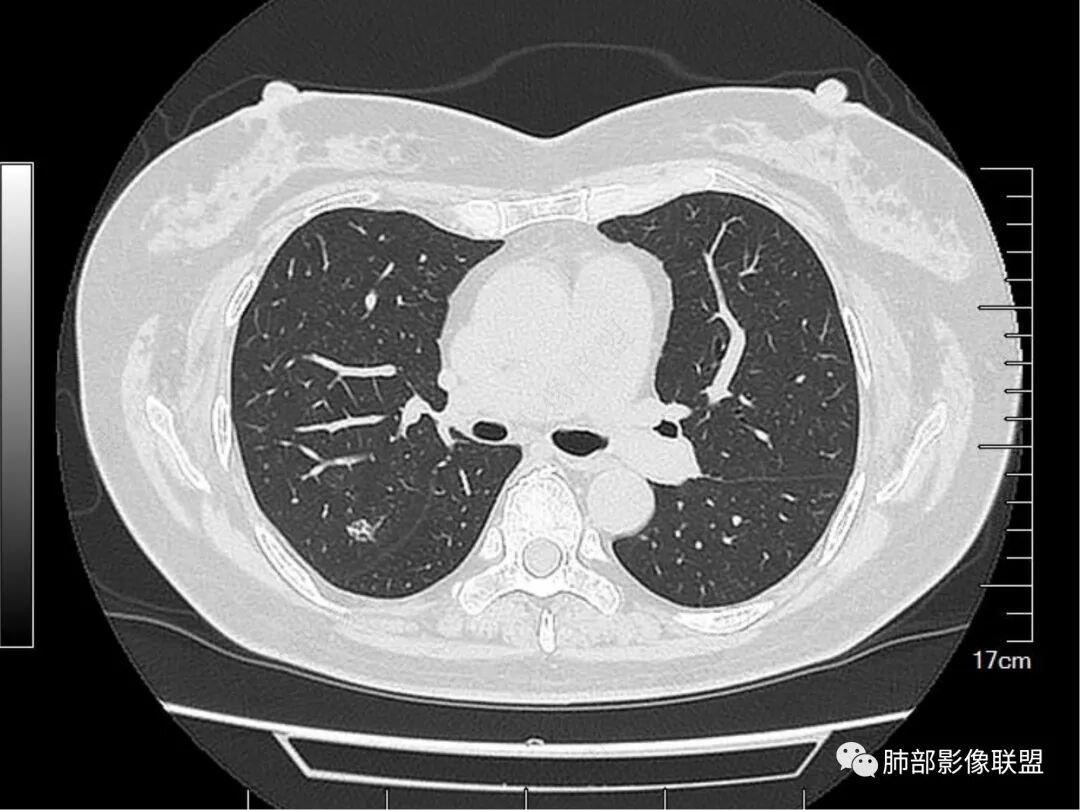

1. 病史简单,老年女性,体检发现肺结节,1年后复查病灶可疑稍增大。

2. 首先定位。这个病变位于胸膜下、肺内病变没问题。请仔细看箭头所示的条索影,我感觉像小叶间隔。